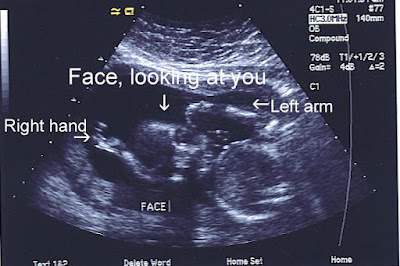

Here, the baby is looking at you again. Its right hand is up by its face.

And here is baby's profile. It really didn't want to give us this picture. It wanted to look at us the whole time. And it was very active. Are we going to have a hyper baby on our hands??